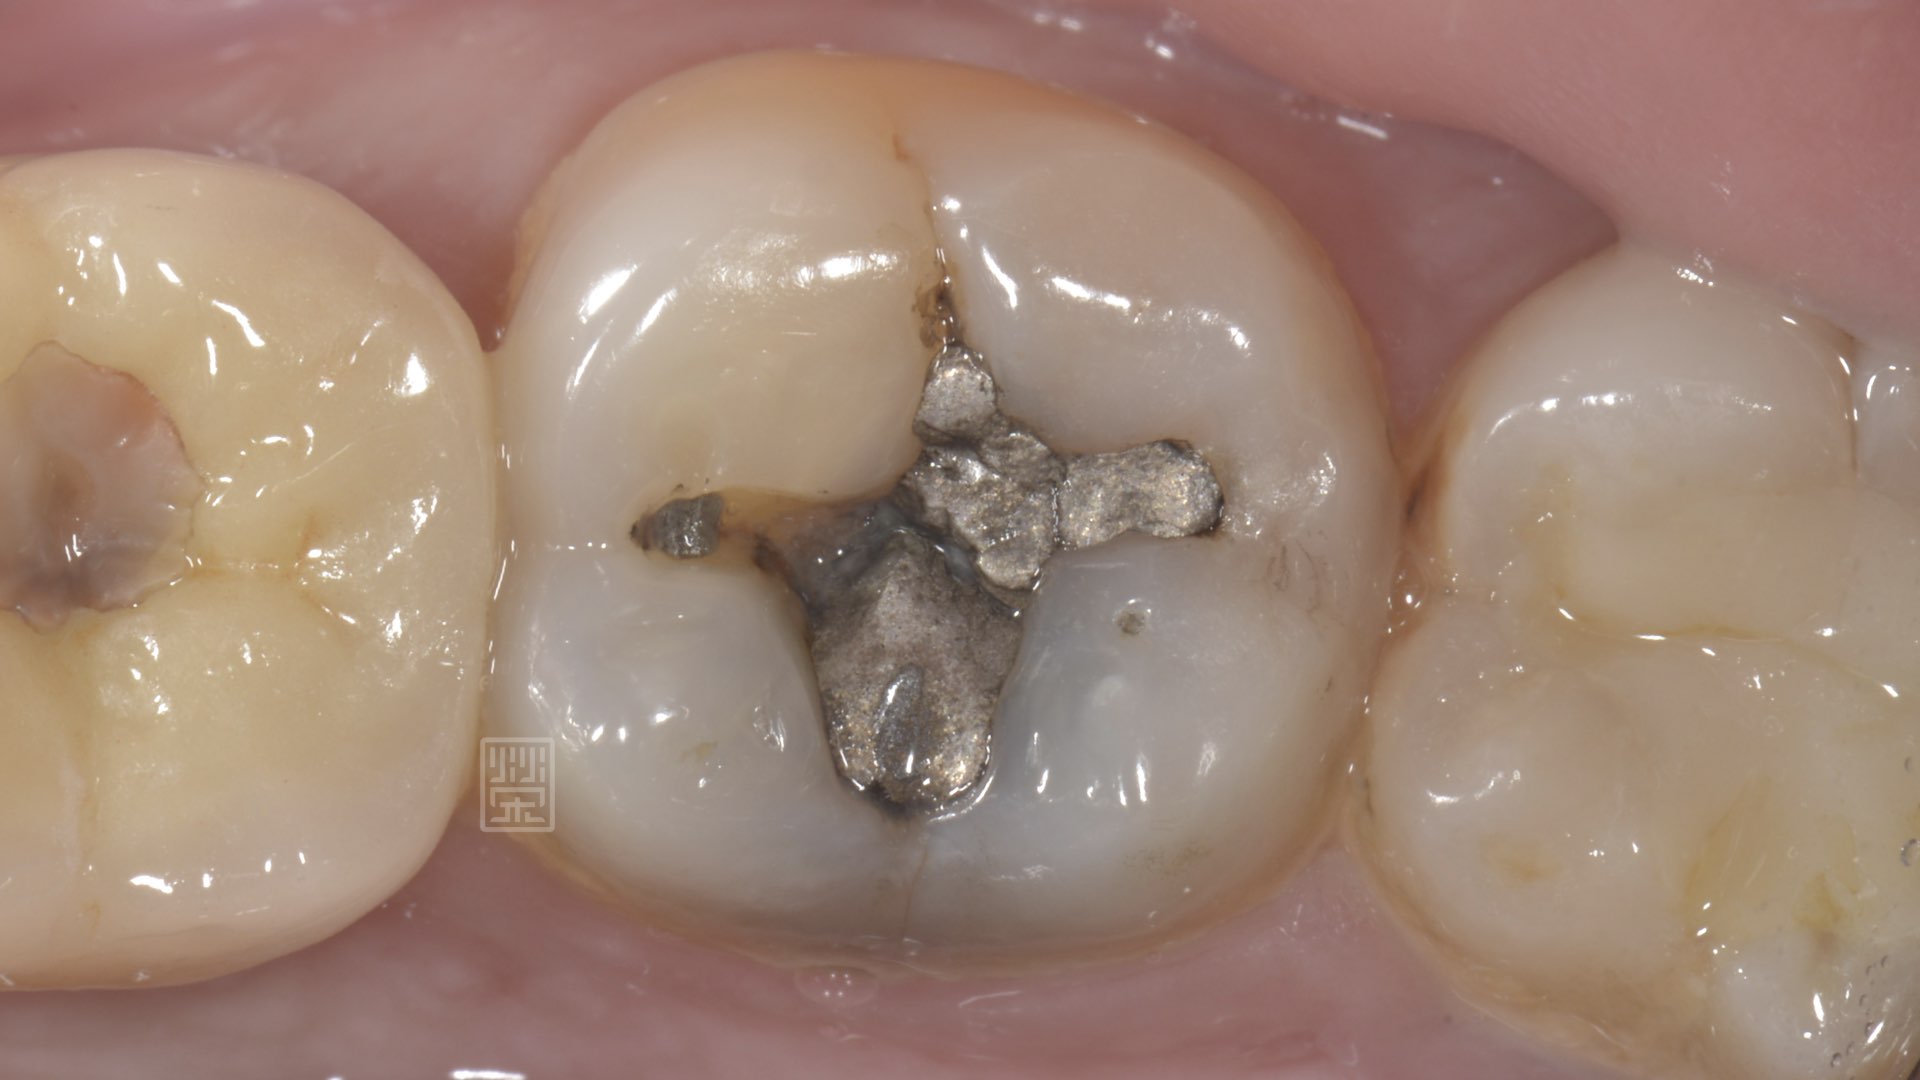

蔡先生常常會覺得左邊牙齒咬起來酸酸的,最近覺得之前填補物好像掉了一些塊,來榮醫師門診檢查,檢查後發現,除了填補的銀粉缺了一塊之外,在舌側地方,牙齒裂掉了。

首先榮醫師先將舊有的銀粉清除,清除後發現雖然咬合面沒看到新蛀牙,但是銀粉底部卻有蛀牙的部分,估計是裂痕長期下來,造成細菌滲漏(microleakage)而產生的蛀牙,所幸蛀牙與裂痕不會非常深,將較薄的牙齒修行後,利用全瓷嵌體覆蓋上去,恢復功能與美觀,讓蔡先生不再擔心不小心咬到這顆牙齒時,突然來的痠痛。

銀粉下牙齒蛀牙